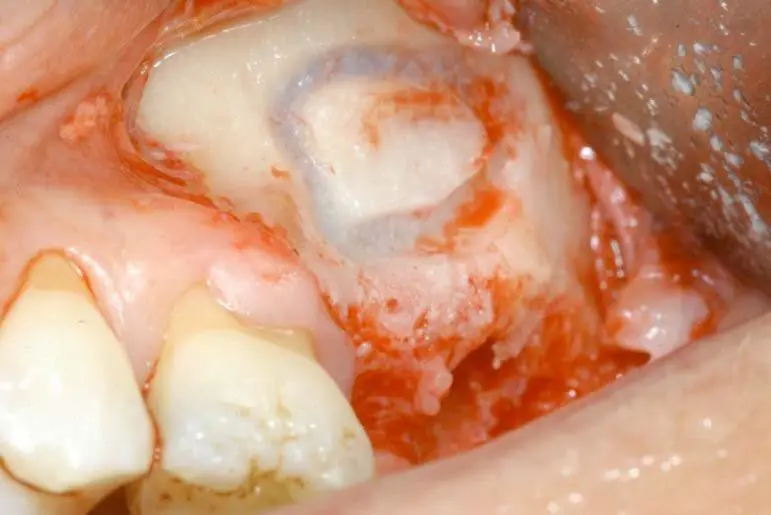

Piezosurgery: Nguyên lý cắt chọn lọc giúp nâng xoang không rách màng

Tìm hiểu nguyên lý Cắt chọn lọc (Selective Cut) của máy Piezosurgery Mectron. Giải pháp nâng xoang an toàn, không rách màng Schneiderian, giảm biến...